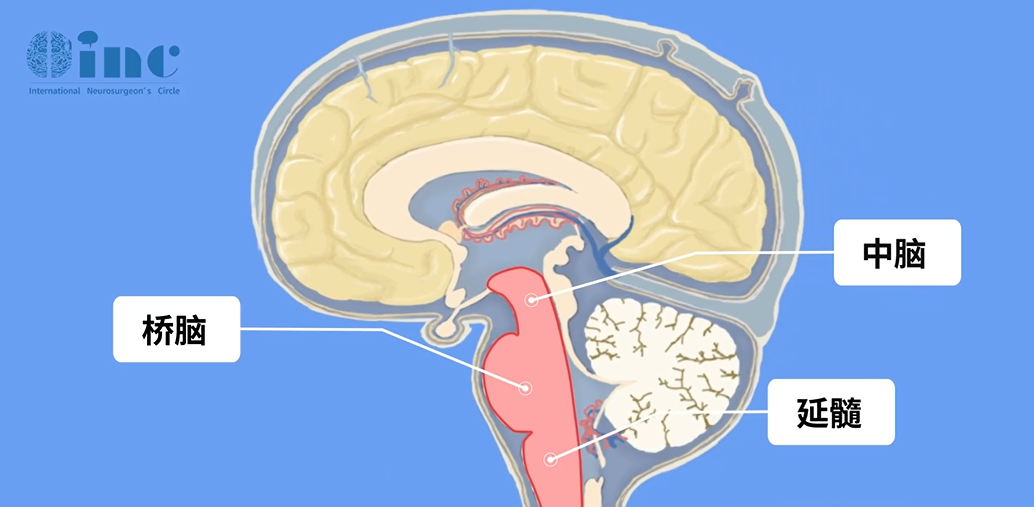

自從早期神經(jīng)外科手術(shù)以來,腦干腫瘤曾長期被認(rèn)為是無法手術(shù)治療的腫瘤。這取決于腦干這一位置的復(fù)雜性——腦干處于大腦的“中心區(qū)”,毗鄰許多大腦重要神經(jīng)中樞,周圍密集了各種神經(jīng)血管,“手術(shù)禁區(qū)”“無法手術(shù)”、“致殘率高”、“復(fù)發(fā)率和致死率高”長久以來成了腦干腫瘤的代名詞,甚至連對腦干病變的活檢也盡量避免。

腦干所處位置示意

當(dāng)然,也不是所有的腦干膠質(zhì)瘤預(yù)后都很糟糕,預(yù)后和治療方案取決于腫瘤的組織學(xué)特征和在腦干內(nèi)的位置。根據(jù)腦干膠質(zhì)瘤的侵襲程度可以簡單的分為兩大類,彌漫性腦干膠質(zhì)瘤(最常見于腦橋)和局灶性腦干膠質(zhì)瘤(大多位于中腦和延髓)。

兒童中,起源于腦干(中腦、腦橋和延髓)的膠質(zhì)瘤占全部中樞神經(jīng)系統(tǒng)(CNS)腫瘤的10%-20%。腦干膠質(zhì)瘤具有異質(zhì)性,從幾乎無需治療的低級別腫瘤到盡管積極治療仍迅速致命的高級別腫瘤都有發(fā)生。預(yù)后和治療方案取決于腫瘤的組織學(xué)特征和在腦干內(nèi)的位置。